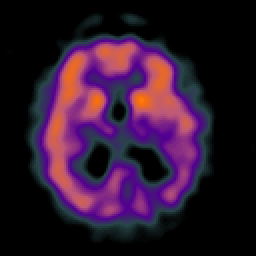

Alzheimer's disease: Perfusion SPECT -- Slice #28

Tour 2: Next/Previous/Start: Here is a mid-ventricular slice which demonstrates the commonest finding in functional imaging of Alzheimer's disease. (Check the corresponding anatomic image by choosing the MR-T2 tickmark on the timeline, or by using the arrow buttons at right) The dark blue regions in the parietal lobes represent areas of decreased blood flow or perfusion. This reduction in blood flow is due in part to the underlying atrophy, in part to the presence of diseased brain, and in part to the functional "disconnection" of this from other brain regions affected by the disease.